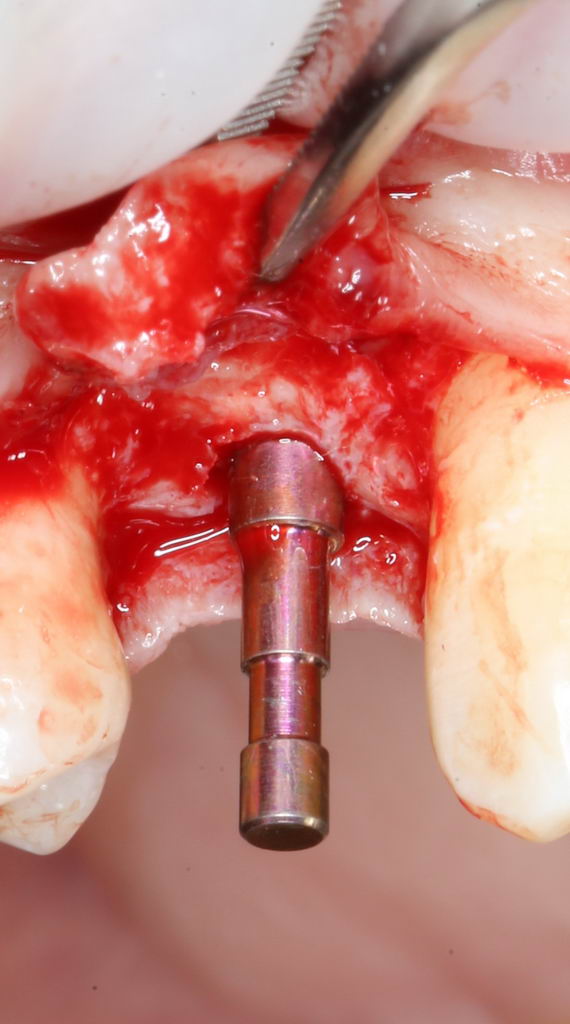

Больше нам абатмент TempBase не нужен, мы его убираем:

Без абатмента можно оценить позиционирование имплантата по глубине погружения. Напомню, что XiVE — это субгингивальная имплантационная система, поэтому ортопедическая платформа имплантата должна находиться на уровне костной ткани. Что и было выполнено в нашем случае.

И, коль всё в порядке, переходим к следующему этапу операции — установке формирователя десны.

Установка формирователя десны.

Одномоментная установка формирователя десны позволяет сократить время и удешевить лечение — ведь по мере интеграции имплантата мы получаем нормально сформированный контур десны, готовый к установке протетической конструкции. Но это возможно лишь тогда, когда с объемами мягких тканей в области имплантата всё в порядке. То есть, как раз в нашем случае.

В CLINIC IN используют только одноразовые формирователи и только один раз:

С учётом клинических условий, мы подобрали к установленному имплантату формирователь Slim (без расширений) высотой 3 мм: